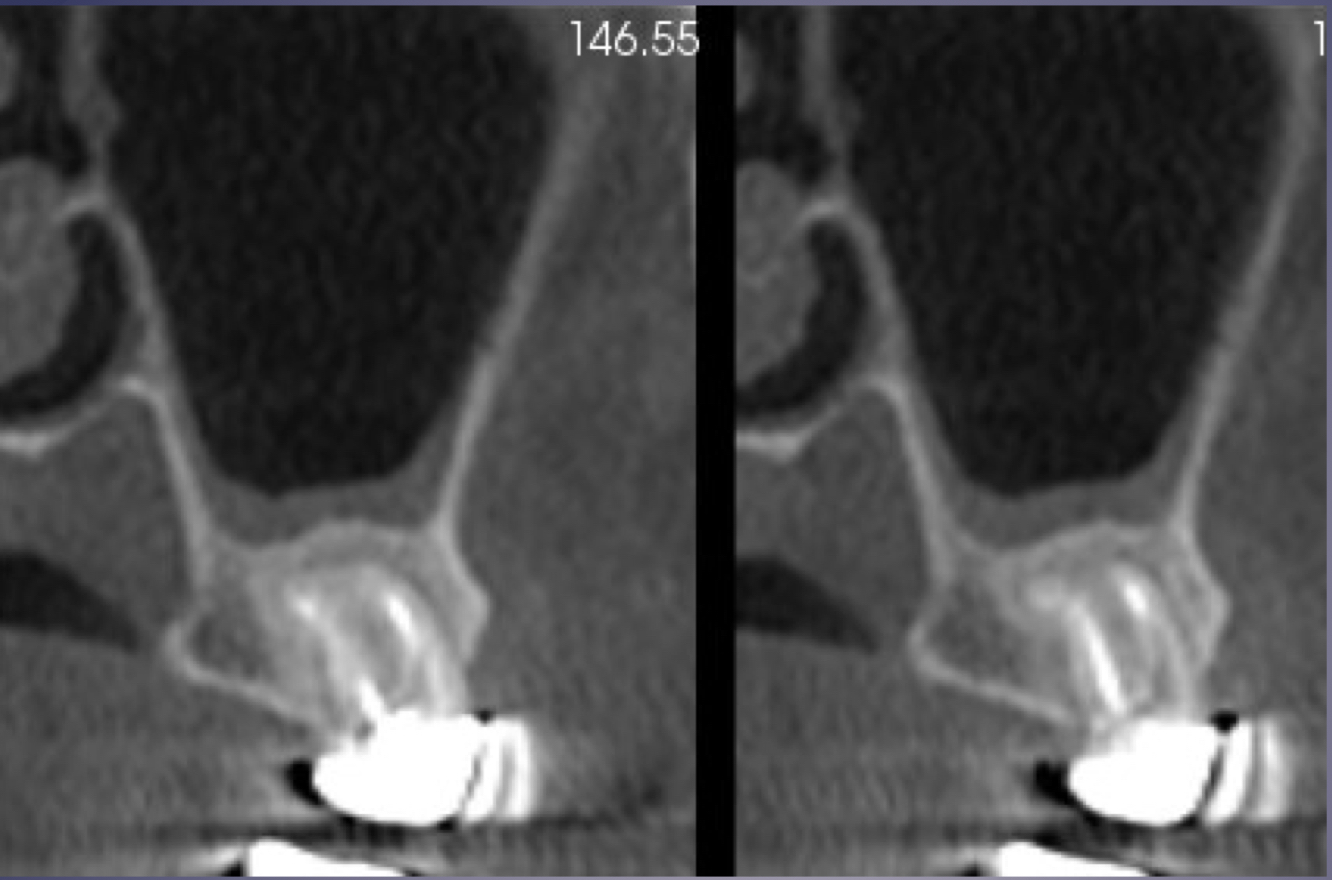

in maxillary M lift floor of max sinus!

elevation/displacement of floor f maxillary sinus

periosteal bone formation in floor of maxillary sinus

periostitis and mucositisÂ

mucosal thickeningÂ